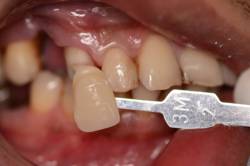

干货集结:

快门 1/125 、 光圈 F25 、 ISO 100

拍摄主体面向光源,不可多反光

比色板与牙齿保持于同一水平线